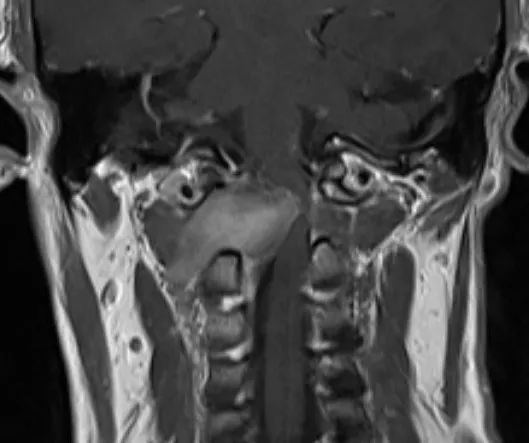

脊柱脊髓外科主任仇继任主任医师对罗先生的病情非常重视,为了查明原因,立即给罗先生完善了相关检查,并对罗先生的症状和体征进行详细分析。各项检查回报后证实了仇继任的考虑,患者第1颈椎椎管内长了一个肿瘤,且位置非常贴近脑干延髓生命中枢,由于特殊解剖生理特点,此处的肿瘤易并发四肢瘫痪和呼吸功能障碍,甚至危及生命。该部位的手术难度大,操作技术要求高,术中处置不当极易导致患者呼吸心跳停止,因此在治疗上存在较大的困难。

为了解决罗先生颈椎上的“定时炸弹”,缓解肢体麻木、行动不便的问题,仇继任及其团队针对罗先生的病情结合术前CT、MRI等影像资料,对治疗方案进行反复讨论和研究,制定了最佳的手术方案——显微镜辅助下精准切除高位颈椎椎管内肿瘤手术。

经过充分的术前准备,仇继任及其团队如期为罗先生进行手术。手术过程中发现肿瘤组织与延髓神经组织粘连紧密,手术难度进一步增大。凭借着精湛而熟练手术技巧及默契的团队配合,仇继任在显微镜下仔细分离肿瘤与脊髓神经组织、精确止血。经过2小时的紧张奋战,手术顺利结束。术后在科室全体医护人员的精心护理下,患者右侧下肢疼痛、麻木症状明显缓解。由于术中未破坏关节突关节,脊柱稳定性得到大部分保留,罗先生术后很快便能起床活动,术后1个星期出院,1个月后随访恢复良好。